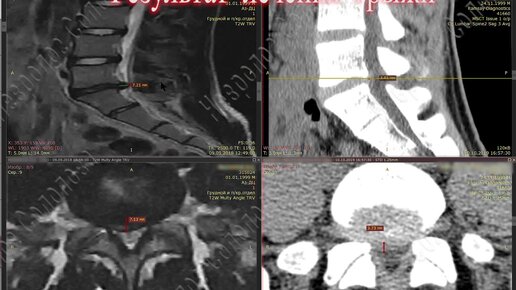

Результат лечения массивной грыжи 8,5 мм!